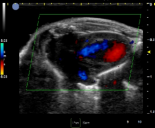

小鼠-腹主动脉彩色血流 小鼠-腹主动脉频谱多普勒 小鼠-左心室短轴 小鼠-心脏彩色血流